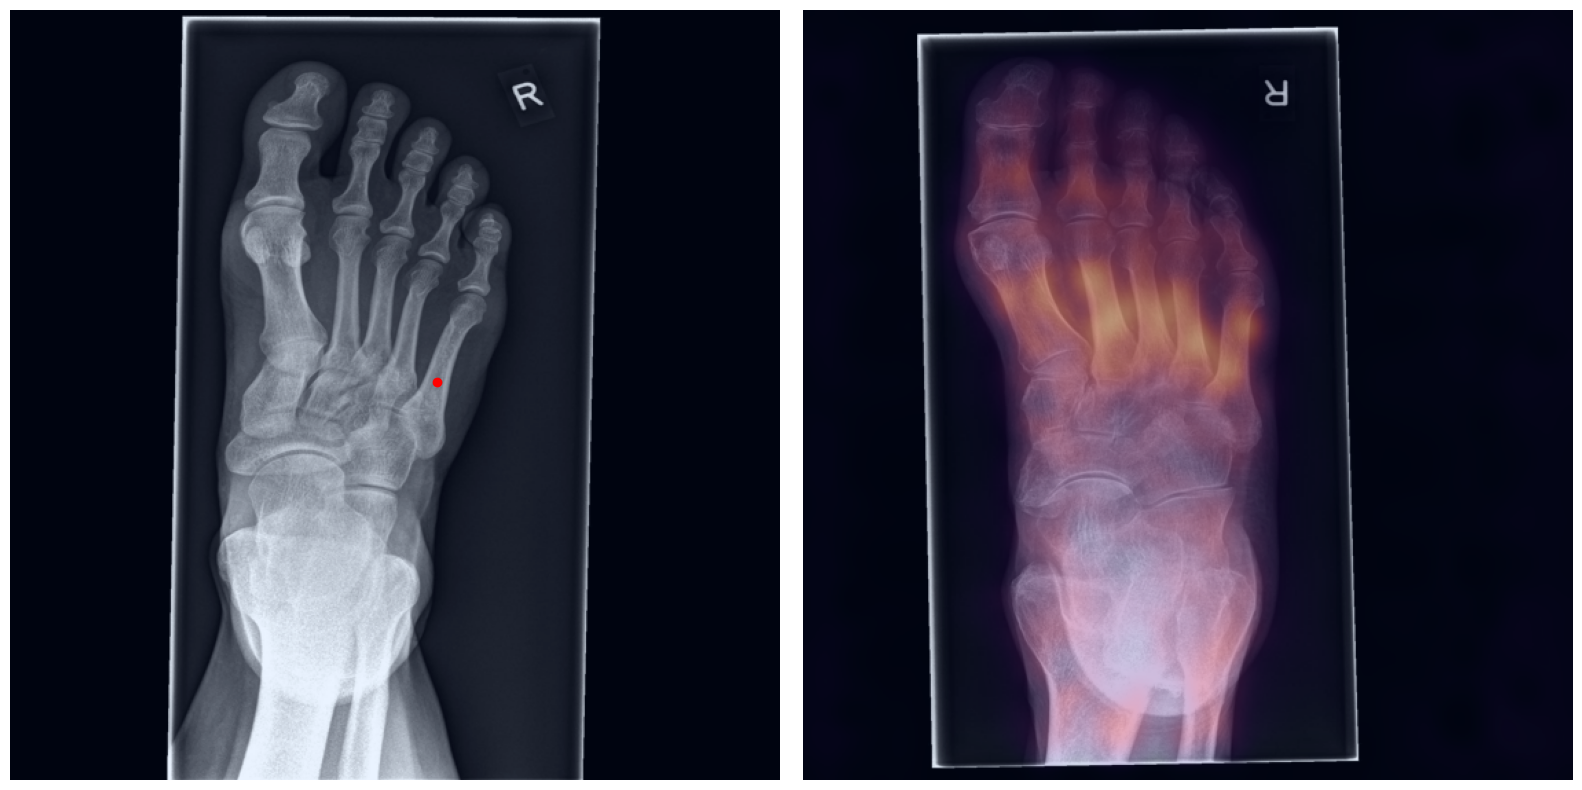

Artificial intelligence (AI) has shown great potential in assisting radiologists with musculoskeletal (MSK) assessments across various anatomical regions1,2,3,4. However, most existing tools are narrowly tailored for specific anatomies or rely on segmentation-based methods as a basis. To address these limitations, we propose a versatile and generalist AI-based approach for landmarks matching. In contrast to typical generalist landmark matching approaches that depend on automatically identified, optimally descriptive landmarks5,6,7, our use-case has to be based on manually selected landmarks tailored for MSK measurements. As these landmarks are potentially subotimal for precise matching, we employ an AI-based method8 that first performs multi-scale dense image matching between the reference and target images independently of the landmarks. The AI uses a combination of transformer and convolutional neural networks to establish a multi-resolution descriptive feature representation of each position within the images, allowing to define correspondences between the reference and target images. In a subsequent step, landmark positions are transferred to the target image based on these correspondences, with the determination of final locations benefiting from the redundancy of the dense matching. This enables robust automation of landmark matching from a reference patient across an entire cohort of target patients. The approach is anatomy-agnostic, enabling the use of the same backbone model for a wide range of anatomical regions and MSK measurements. For more detailed information we refer to our paper.

Once a correspondence between the reference and target radiographs is established, landmark matching can be performed in real-time. This process enables the alignment of individual points and allows for the definition of a predefined set of landmarks that can be mapped onto the target patient. These predefined landmarks can be customized for the automated calculation of specific measurements, which, once defined on a reference patient, can be consistently and automatically transferred to any radiograph within the target cohort.

The process of establishing a dense match between two images relies on abstract feature representations for each position in both the reference and target images. To better understand which information is encoded by the AI, we examined the feature similarities between a specific position within the reference image and the entire target image. Our findings show that the AI captures both semantic and texture features. The matching process utilizes this encoded information, along with precise positional data, to create a reliable mapping between the images.

From Novice to Expert: Annotation Through Imitation